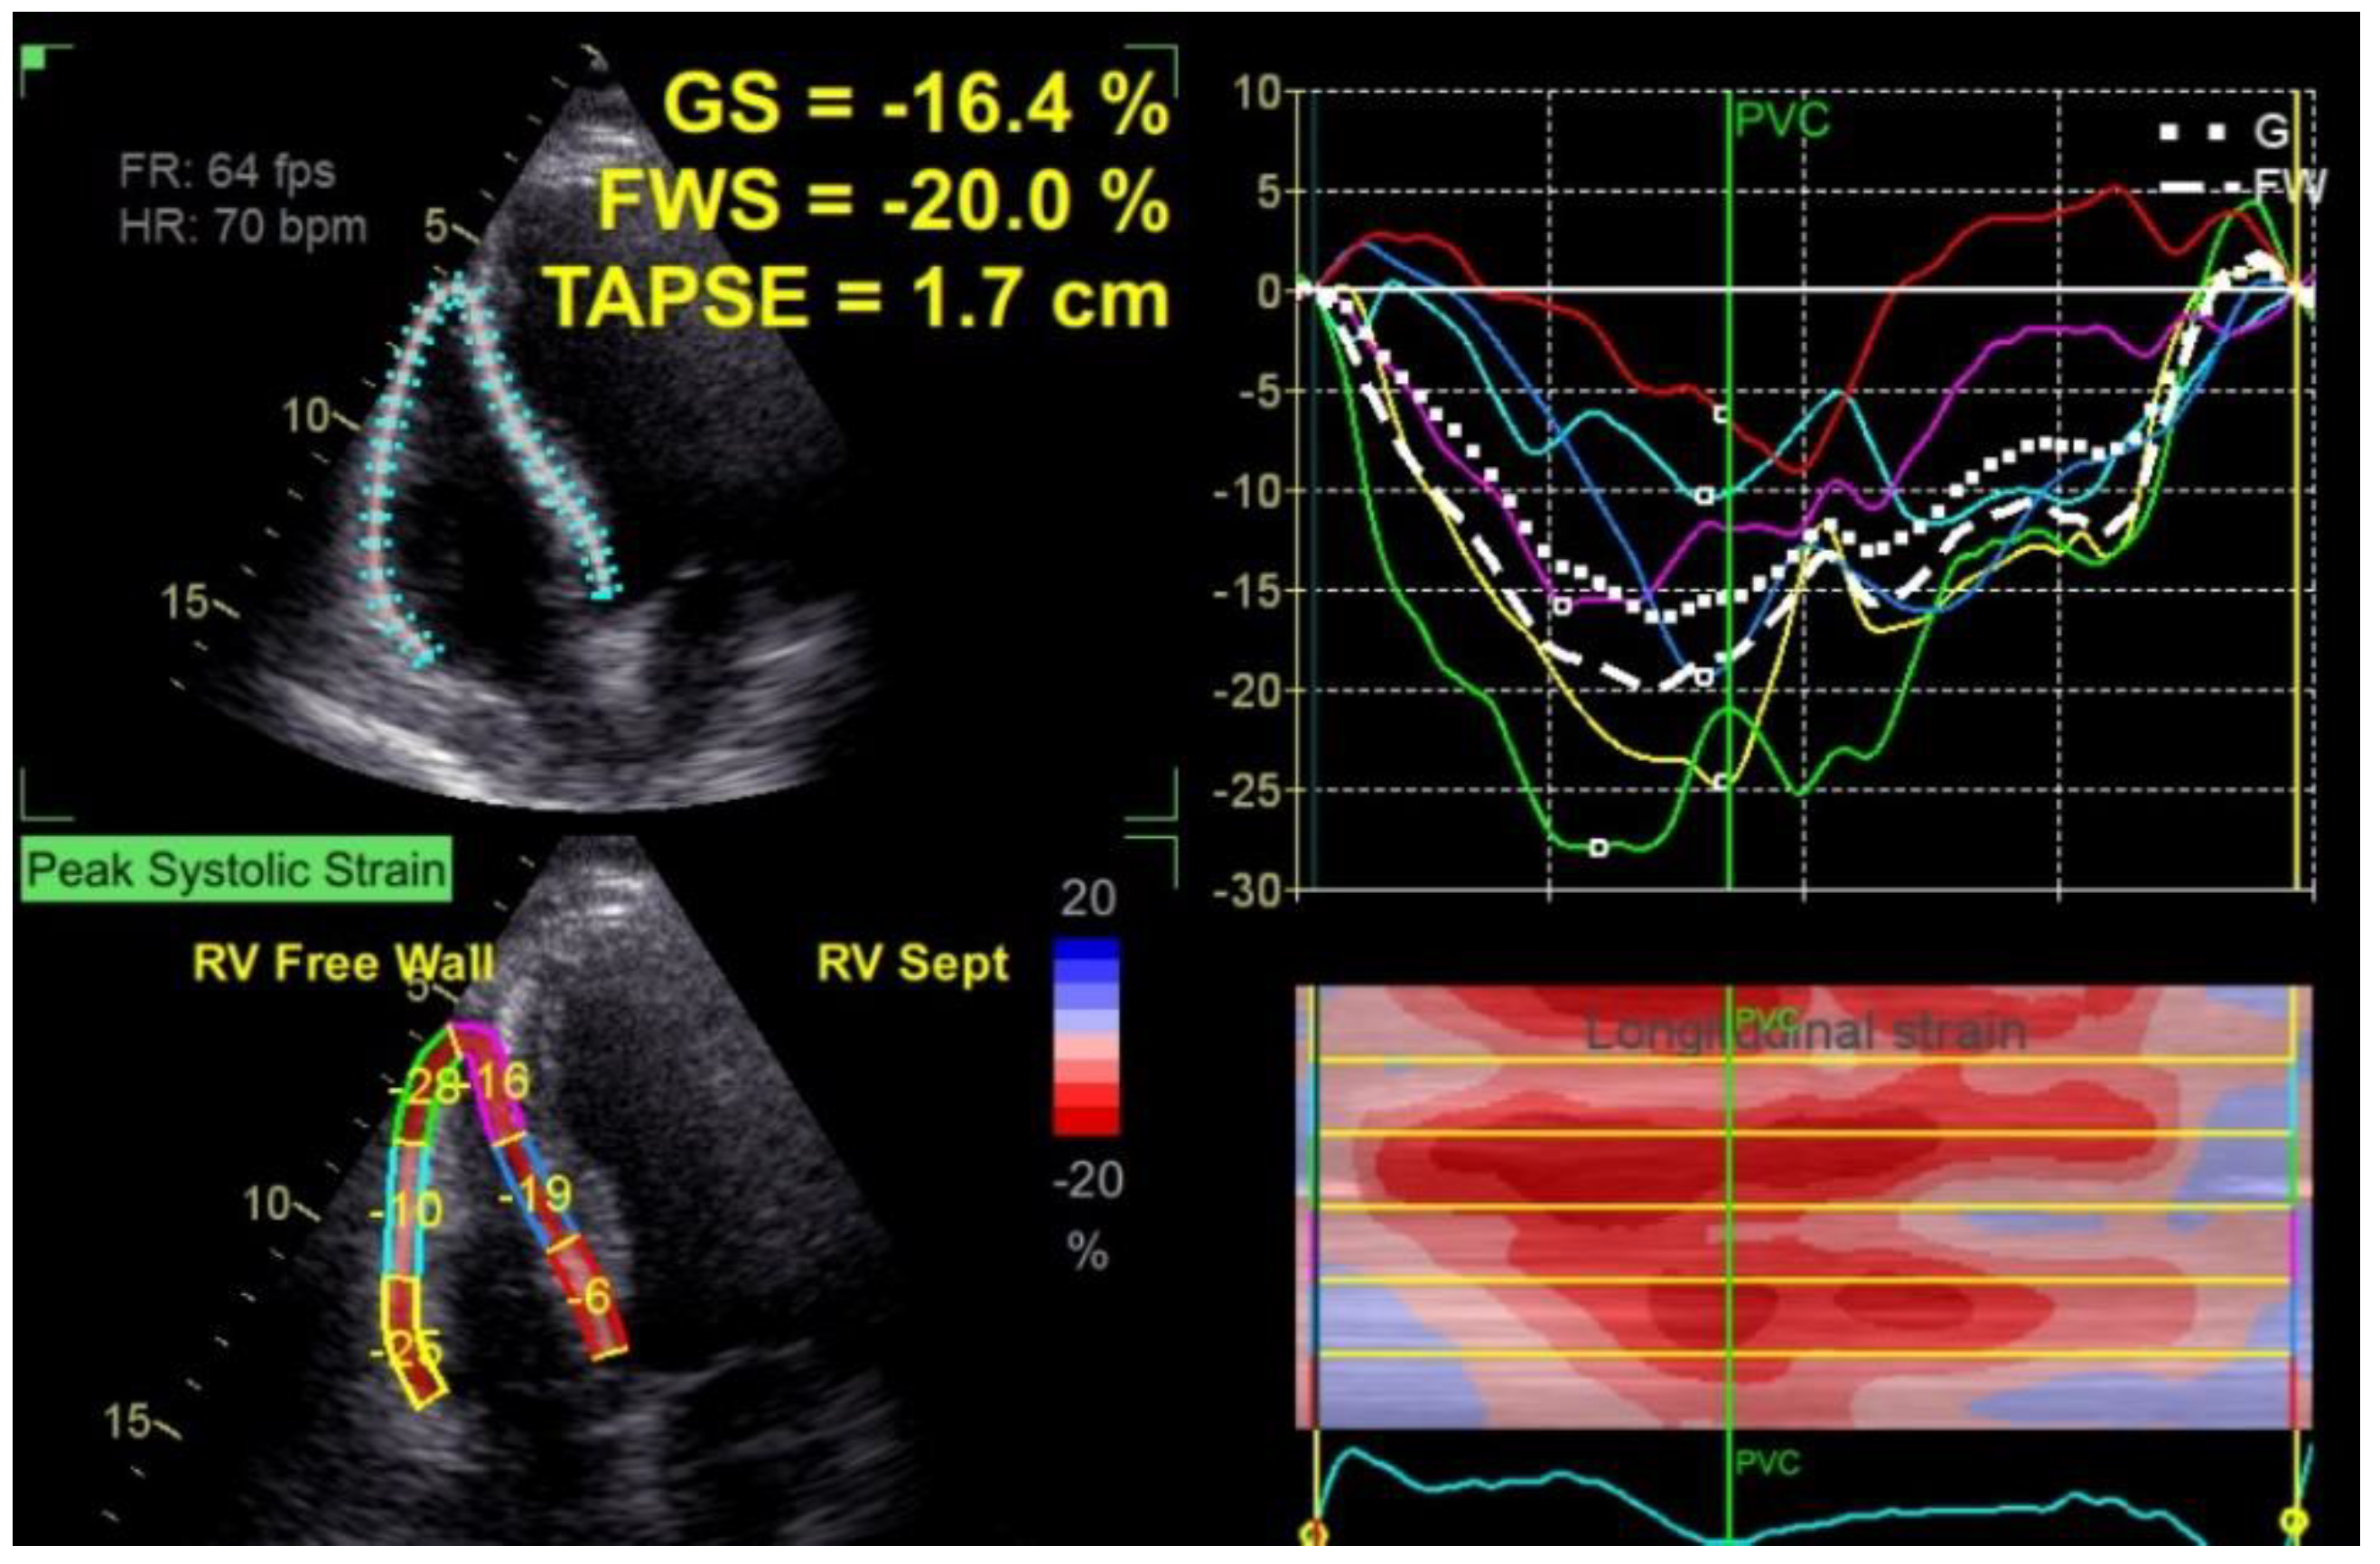

2.1.2. Right Ventricle Echocardiographic Evaluation